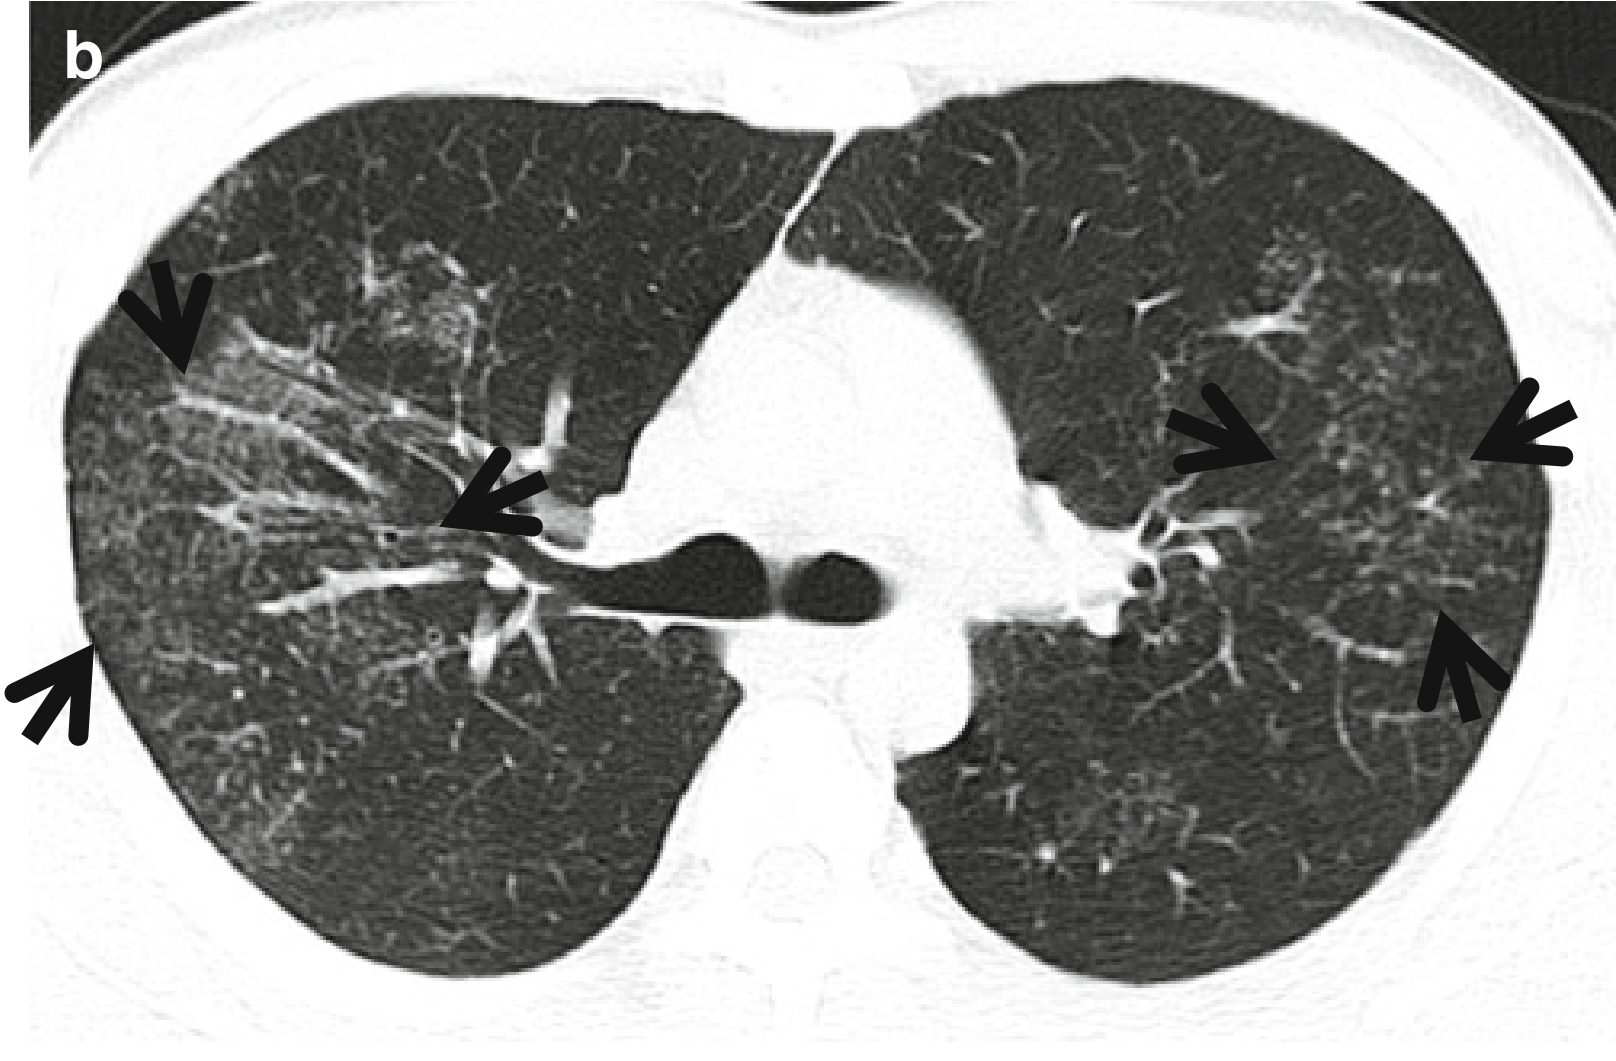

图1,CT星系征。男,23岁、肺结节病患者。连续薄层CT扫描(层厚=2.5mm)于右肺上叶支气管水平可见多发星系征(箭头所示),由多个小结节和周围多发非常小的卫星病灶组成、以右肺上叶最为明显。纵隔窗(此处未给出)可见纵隔和双侧肺门增大的淋巴结影。

常见疾病:在CT上,星系征见于肺结节病和活动性肺结核(表1)(图2 和图3)。肺结节的CT星系征与其他征象一样,通常分布在中、上肺野,但在下肺野也可见到。